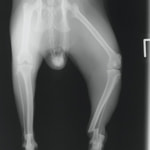

ペルシャ猫 11ヶ月齢 雄

他院にて左大腿骨遠位の成長板骨折(salter-harrisⅠ型)が認められており、治療相談を目的として来院。当院にて、キルシュナーワイヤーを用いたピンニングにより骨折部位の整復を行いました。術後の経過は良好で、現在も経過観察中です。

術前レントゲン

術後レントゲン

Arthrex社のターゲティングデバイスを用いてピンニングの位置を調整することで、確実な固定を行っています。当院ではこの手術器具以外にも、人の手術にも使用される様々な器具を導入し、手術精度を高め、また医療メーカーと新しい器具の開発、試作にも取り組んでおります。